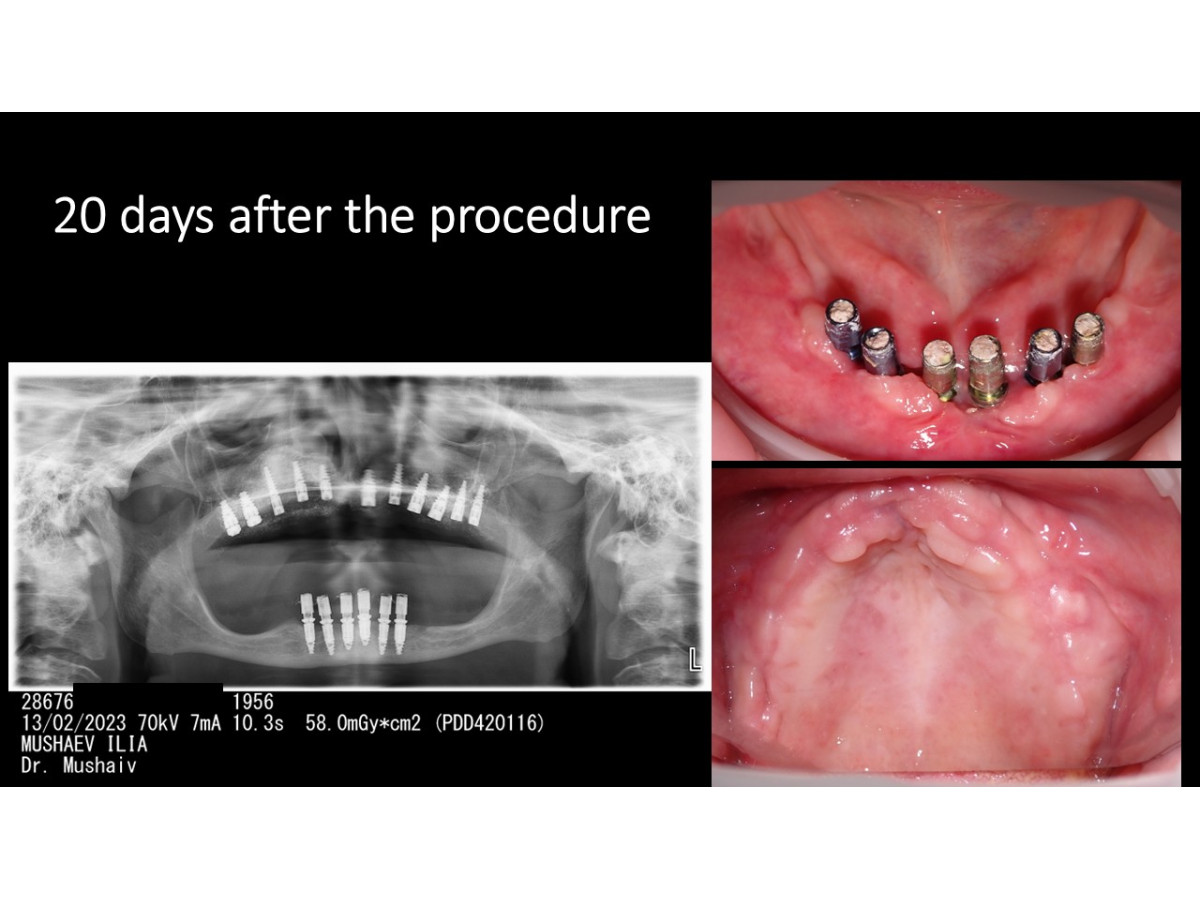

Clinical case: Dental implantation with & without immediate loading, bone augmentation, nasal and sinus lifting, soft tissue monitoring.

Dentist: DDS PhD Ilia Mushayev/Sidhedent, DMi (Israel)

Clinical case, dental implantation